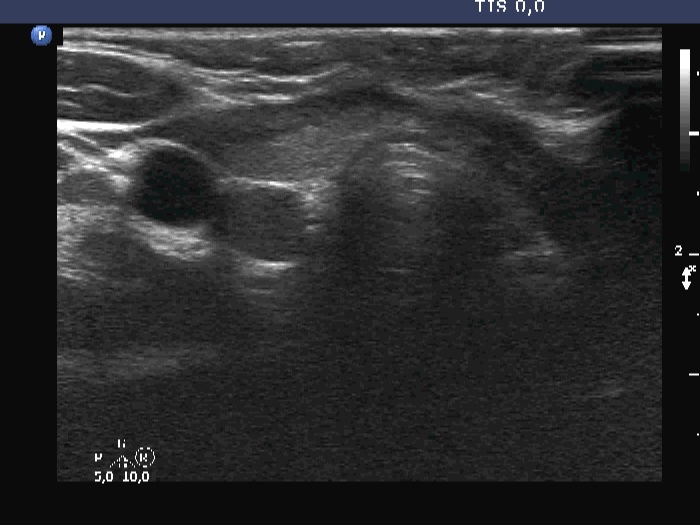

Ultrasonography. The thyroid was echonormal and had some minimally hypoechoic areas. A thick connective tissue band crossed the right lobe. Dorsal to this fragment the thyroid was very hypoechoic. On transverse scan, this area seemed to be a nodule. However, analysis of multiple sections revealed that this area was not a true nodule.

In this boy, the thick connective tissue hindered the penetration of the ultrasound wave, therefore the dorsal structure became darker, hypoechoic. -